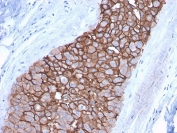

Immunohistochemistry analysis of FFPE human breast carcinoma tissue using protein microarray validated HER2 antibody (clone ERBB2/3092). Brown chromogenic signal indicates HER2-positive membranous staining in tumor epithelial cells. Heat-induced epitope retrieval was performed by boiling tissue sections in pH 6 10mM citrate buffer for 10-20 minutes, followed by cooling at room temperature prior to antibody incubation.

IHC staining of FFPE human breast carcinoma with HER2 antibody (clone ERBB2/3092). HIER: boil tissue sections in pH6, 10mM citrate buffer, for 10-20 min followed by cooling at RT for 20 min.